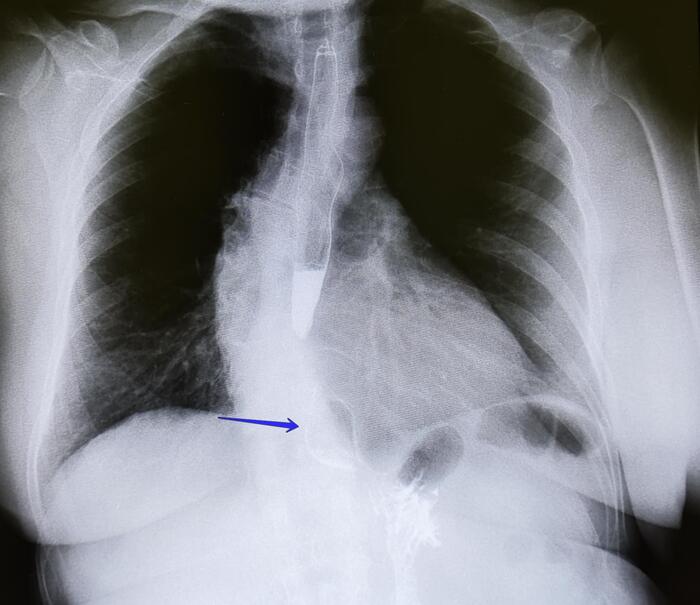

Отсутствие деструкции окружающих тканей:

Эностоз не вызывает разрушения окружающей костной ткани и не сопровождается периостальной реакцией.

Отсутствие мягкотканного компонента:

Эностоз не сопровождается образованием мягкотканного компонента или внекостного распространения.

Дифференциальная диагностика

Эностоз необходимо дифференцировать с другими образованиями костной ткани, такими как:

Остеоид-остеома.

Остеобластные метастазы.

Склерозирующие дисплазии костей.

Для уточнения диагноза могут быть использованы дополнительные методы визуализации, такие как КТ или МРТ. В сомнительных случаях может потребоваться биопсия.